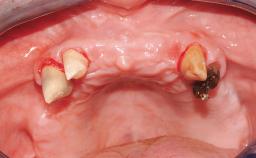

Immediate Loading of Six Implants in the Mandible and Six Implants in the Maxilla and Final Restoration with Full-Arch CAD/CAM Metal Framework FDPs Involving Digital Planning and Guided Surgery

Immediate loading of dental implants is increasingly popular with clinicians and patients. The idea of delivering a restoration directly after implant insertion,combined with a less invasive procedure (flapless protocol), has made treatment protocols involving dental implants more accessible to dentists and patients. However,immediate-loading concepts require sophisticated and exact planning. To facilitate this, conventional panoramic tomographs and periapical radiographs are often taken with the patient wearing a radiographic template simulating the preoperative prosthetic design. However, these radiographs do not provide all the necessary information. In addition, some protocols call for conventional surgical templates fabricated on the diagnostic cast. These will inform the bone drilling points and drill angles, but do not reference the underlying anatomical structures or provide exact 3-D guidance.

Case Type Edentulous Maxilla

# of Implants 12